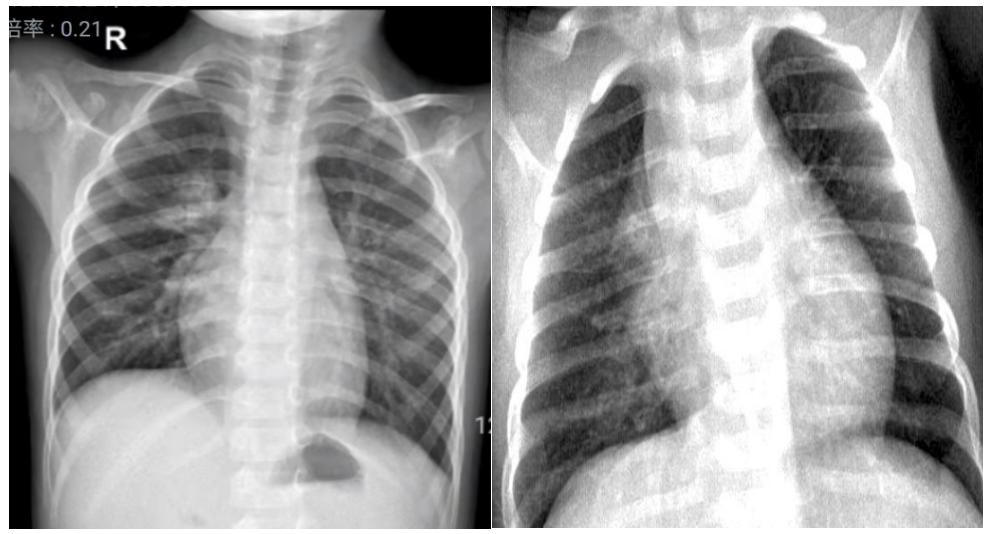

1、帆型:单侧分布,致密均匀,呈三角帆形,内缘位于纵膈内,外缘自内上斜向外下达中肺中带,边缘锐利。如下图4所示。

图4示:船帆型胸腺影

2、三角形:单侧,致密均匀,三角形尖端指向肺门,内缘与纵膈相连,下缘位于水平叶裂位置,边缘均清晰锐利。如下图5所示。

图5示:三角形胸腺影